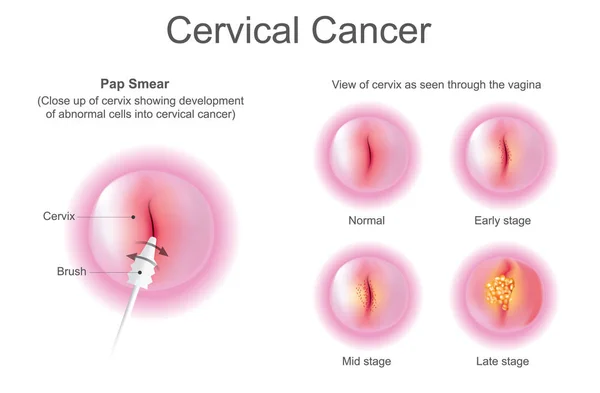

PAP Smear & Cervical Cancer

Cervical cancer is one of the most preventable cancers affecting women — yet it remains a

leading cause of cancer-related deaths in India due to lack of early screening. A simple Pap

smear test can detect precancerous changes in the cervix, allowing early treatment and

complete recovery before cancer ever develops.